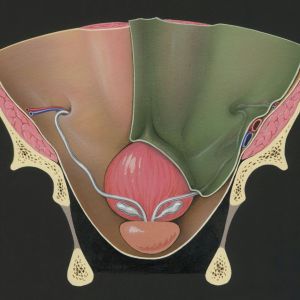

Chirurgie generală și proctologie

Chirurgie generală și proctologie